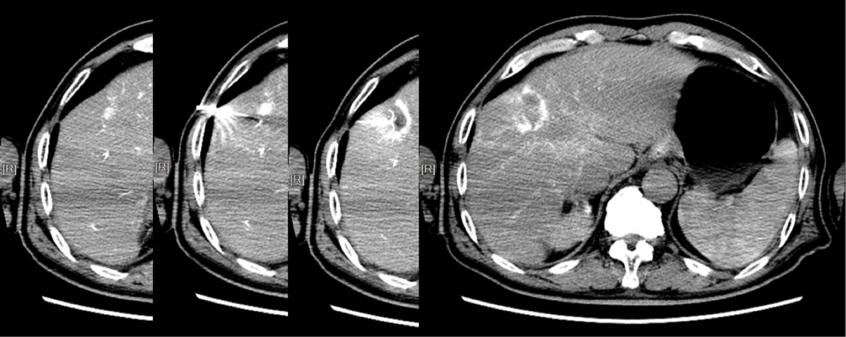

上腹部MRI:

复查:2016-01,TACE 2月后,肝内无活性病灶 、乙肝病毒载量转阴。

2016-01~2017-07,复查次MR及CT:肝内无瘤,无血管侵犯、肝外转移,坚持口服索拉非尼 400 mg,bid

复查:第2次 RFA消融后3月,复查MR无活性病灶。(至2020-04 第3次复发,间隔 30个月。) 第三阶段方案